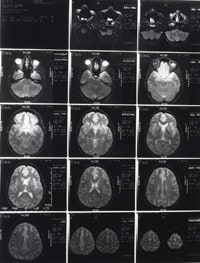

Primary microcephaly (MCPH) is an autosomal recessive inherited disease characterised by a small, but architecturally normal brain. Although the disease results in mild to moderate, non-progressive mental retardation, development is otherwise generally normal. Dr Jacqueline Bond tells us about her work on MCPH and, in particular, the role of microscopic imaging in helping to understand brain development.

Our aim, within the Section of Ophthalmology and Neuroscience, is to determine the causes of human inherited neurological disorders, and in doing so, gain insights into the processes of neurogenesis, neuronal homeostasis and function. One of the interesting features of microencephaly (MCPH) is that although the brain is small, it is otherwise normal and there are no other apparent associated developmental abnormalities. The genes involved in MCPH may, therefore, be expected to have a specific role in neurogenesis but not in other developmental processes. A greater understanding of the genes involved in MCPH and the functional aspects of these genes is likely to contribute not only to improved clinical management of patients affected by this disease but also to a greater understanding of brain development in general.

It is known that ASPM is expressed in the neuroepithelial layer surrounding the ventricles of the brain and that the ASPM protein localises to the spindle poles during mitosis. ASPM is thought to have a role in controlling the fate of neuroprogenitor cells. A progenitor cell can divide in two ways; symmetrically to make two identical progenitor daughter cells; or asymmetrically when the cleavage furrow in the cell is rotated by 90 degrees, to produce one daughter progenitor cell and one specialised brain cell i.e a neuron. The change in the type of daughter cells is related to the position of cell fate determinants on the cell membrane and the way in which these determinants are allocated to daughter cells during cell division. Normally, ASPM appears to be involved in maintaining symmetrical cell division increasing the number of progenitor cells and providing a high capacity for neuron generation. In MCPH, the maintenance of symmetrical division fails resulting in fewer progenitor cells and a limited capacity to produce neurons. The neurological developmental window is very small, starting at about week five of foetal life and finishing before birth. If insufficient progenitor cells are made during this period, small brain size results. MCPH, therefore, is not linked to any apoptotic or degenerative mechanism but is believed to be a failure in neuron production.

While functional gene studies will help to learn more about them process of neurogenesis and MCPH, the problem with MCPH is that it occurs very early in utero and there is very little chance of being able to intervene to influence these events in a developing foetus. There are also no therapies currently available that can prevent or alter the course of the disease. However, the identification of genes involved in MCPH has enabled in utero diagnosis at about 16 weeks gestation and early recognition of the disease may help to maximise developmental potential through supportive care once the infant is born. Knowledge of gene mutations also enables family screening and the identification of MCPH carriers. With genetic counselling this information can help affected families make informed decisions about pregnancies and family planning.